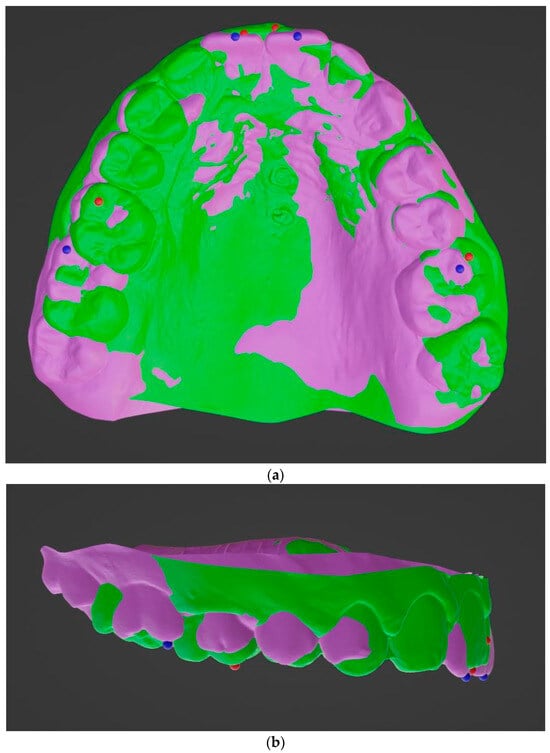

- Becker, K.; Wilmes, B.; Grandjean, C.; Drescher, D. Impact of manual control point selection accuracy on automated surface matching of digital dental models. Clin. Oral. Investig. 2018, 22, 801–810. [Google Scholar] [CrossRef]

- Almeida, M.A.; Phillips, C.; Kula, K.; Tulloch, C. Stability of the palatal rugae as landmarks for analysis of dental casts. Angle Orthod. 1995, 65, 43–48. [Google Scholar]

- Hoggan, B.R.; Sadowsky, C. The use of palatal rugae for the assessment of anteroposterior tooth movements. Am. J. Orthod. Dentofac. Orthop. 2001, 119, 482–488. [Google Scholar] [CrossRef]

- Kim, H.K.; Moon, S.C.; Lee, S.J.; Park, Y.S. Three-dimensional biometric study of palatine rugae in children with a mixed-model analysis: A 9-year longitudinal study. Am. J. Orthod. Dentofac. Orthop. 2012, 141, 590–597. [Google Scholar] [CrossRef] [PubMed]

- Choi, D.S.; Jeong, Y.M.; Jang, I.; Jost-Brinkmann, P.G.; Cha, B.K. Accuracy and reliability of palatal superimposition of three-dimensional digital models. Angle Orthod. 2010, 80, 497–503. [Google Scholar] [CrossRef] [PubMed]

- Choi, J.I.; Cha, B.K.; Jost-Brinkmann, P.G.; Choi, D.S.; Jang, I.S. Validity of palatal superimposition of 3-dimensional digital models in cases treated with rapid maxillary expansion and maxillary protraction headgear. Korean J. Orthod. 2012, 42, 235–241. [Google Scholar] [CrossRef]